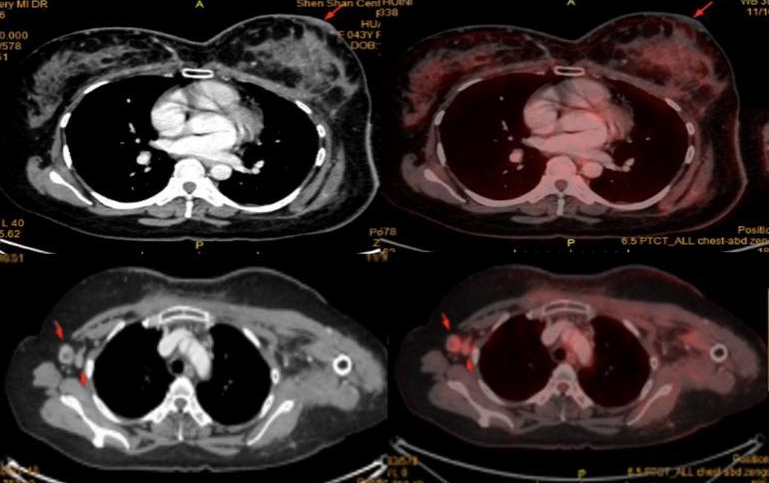

PET-CT:考虑左乳皮皮肤转移伴炎症可能;右侧腋窝淋巴结转移。余未见明显异常。

在完成了全面且详尽的各项检查之后,确诊为:左乳浸润性导管癌保乳术后皮肤及右腋窝淋巴结转移,IV期,三阴型。此时,查体可见前胸壁及背部皮肤弥漫性增厚伴皮革样硬化,符合乳腺癌晚期特征性体征——“铠甲胸”表现。建议患者尽早启动速效治疗方案,若病情持续进展,可能导致呼吸功能受限,显著降低生存质量。鉴于患者长期居住在汕尾地区,为减轻其往返于广州与汕尾之间的舟车劳顿,龚畅教授和乳腺肿瘤内科曾银朵教授再次发起并主持了一次线上多学科联合远程会诊。来自各学科的专家团队齐心协力,为患者量身定制了治疗方案,不仅保障了医疗服务的质量,也减轻了患者的就医压力。

6程后复查乳腺MR、胸部+上腹部CT、乳腺彩超,提示:左乳病灶范围较前明显缩小,右腋窝肿大淋巴结消失。